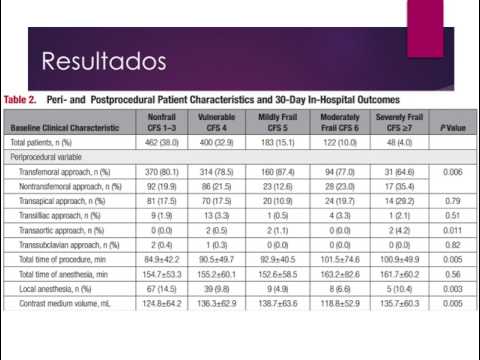

TAVI en pacientes con EAo severa sintomática de bajo riesgo. Dra. Ana Laura Mori. Residencia de Cardiología. Hospital C. Argerich. Buenos Aires